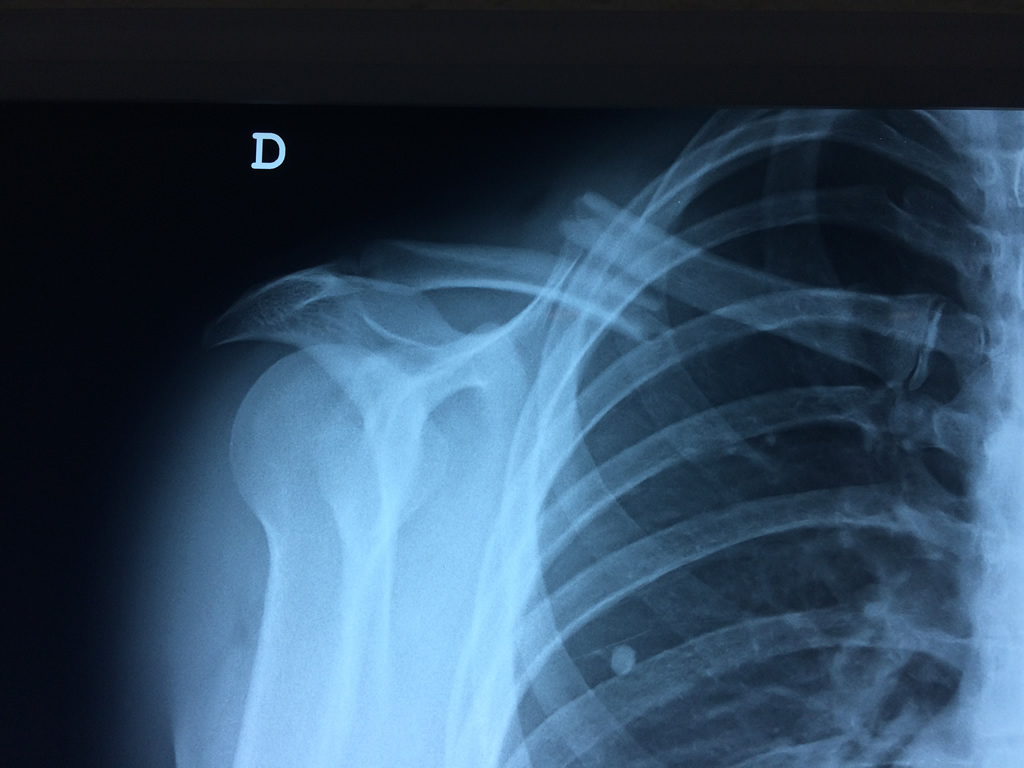

Cirugías de Codos - Clavícula

La clavícula es un hueso largo, con forma de "S" itálica, situado en la parte anterosuperior del tórax. Junto con la escápula forman la cintura escapular. Se puede palpar por toda su longitud y se extiende del esternón al acromion de la escápula, siguiendo una dirección oblicua lateral y posterior.